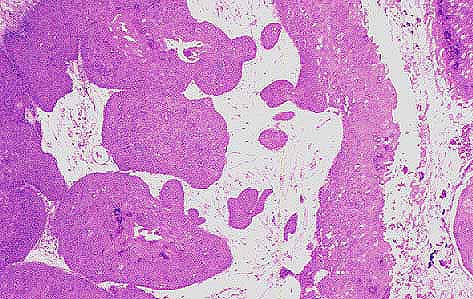

Foto nº3) Proliferación epitelial lobulada de bordes expansivos.